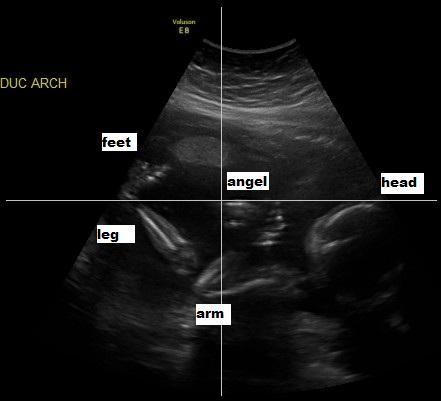

But of all God's miracles in our world, none is more special than this ultra sound of Kendra, taken shortly after we learned that she would be born with Spina Bifida, but before we had any clue how severely she might be affected. I'm gonna post the picture, and you tell me what you see. Right after Jen gave me my ultrasound printout I spotted this, and I relaxed. I knew Kendra was going

to be just fine, and that her future was in greater hands than ours. If you see it, let me know. If you have trouble I'll point it out. Ready, set, GO!!

Sounds like a very wise, very loving preacher! Okay, I'm gonna post another picture - same one - with the surprise pointed out

Do you see Kendra's Guardian Angel right there with her? You may have to lean back a little, but she's there!

Look right at the intersection of the four lines.....and just a little below to the right. There's a face, and you can see her hairline almost on the line. She's right below the word "Angel".